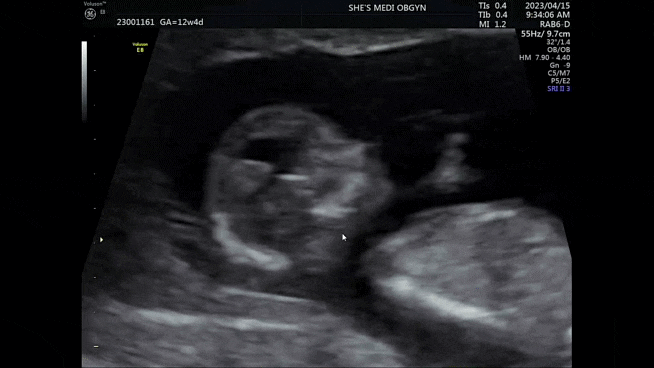

로라의 성별은...?! 임신 초기(9주~12주) 일기

3월 19일 집에가서 밥먹고 아빠한테 과일깎아달라했다 기대하는 표정 제법 욱겨... 친정엄마 밥은 입덧이 ...